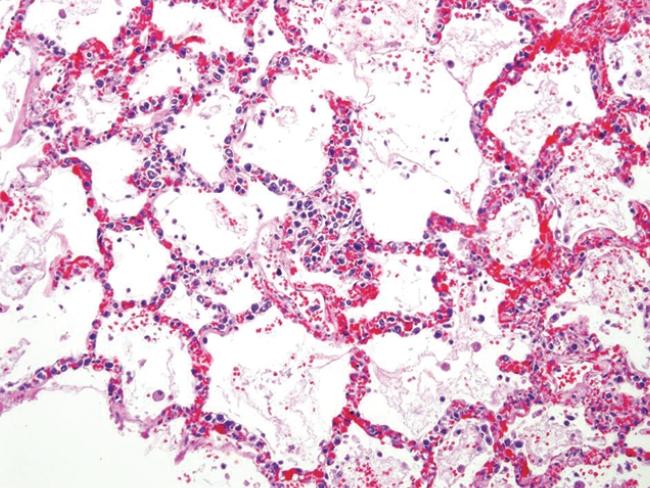

Intravascular Large B-cell lymphoma (IVLBCL) is an exceptionally rare form of non-Hodgkin lymphoma (NHL) distinguished by the preferential growth of neoplastic cells within blood vessel lumen. Challenging to detect and deemed disseminated at diagnosis, this condition is characterized by a highly aggressive, inconspicuous course with a high mortality rate. We describe the case of a 48 year-old African-American female presenting with a two month history of low-grade fevers and malaise. Laboratory data was notable for anemia, thrombocytopenia, elevated liver function tests, and hematuria. An extensive work-up for infectious, rheumatologic and malignant causes was negative. Her symptoms progressed and within two weeks, she was admitted for disseminated intravascular coagulation (DIC). Her course was complicated by diffuse pulmonary hemorrhage and ultimately, care was withdrawn. Autopsy identified widespread CD-20 positive intravascular large B-cell lymphoma with significant hepatosplenic involvement, characteristic of the Asian variant IVLBCL. This case uniquely highlights development of the Asian variant IVLBVL in a previously undescribed race. Identified by its intraluminal vascular growth pattern, IVLBCL generally spares lymphatic channels. Diagnosis and differentiation of this condition from other hematological malignancies via skin, visceral and bone marrow biopsy is imperative as anthracycline-containing chemotherapies may significantly improve clinical outcomes. This article outlines the common presentation, natural course, and treatment options of IVLBCL, along with the histopathology, immunohistochemistry, and chromosomal aberrations common to this condition.

血管内大B细胞淋巴瘤(IVLBCL)是一种极为罕见的非霍奇金淋巴瘤(NHL),其特征为肿瘤细胞优先在血管腔内生长。这种疾病难以检测,在诊断时即被认为已播散,其病程高度侵袭性且隐匿,死亡率高。我们描述了一例48岁非裔美国女性患者的病例,她有两个月的低热和乏力病史。实验室检查结果显示贫血、血小板减少、肝功能检查指标升高和血尿。针对感染、风湿和恶性病因进行的广泛检查均为阴性。她的症状逐渐加重,两周内因弥散性血管内凝血(DIC)入院。她的病程因弥漫性肺出血而复杂化,最终放弃治疗。尸检发现广泛的CD-20阳性血管内大B细胞淋巴瘤,伴有显著的肝脾受累,这是亚洲型IVLBCL的特征。该病例独特地凸显了亚洲型IVLBVL在一个此前未被描述过的种族中的发生情况。IVLBCL以其管腔内血管生长模式为特征,通常不累及淋巴管。通过皮肤、内脏和骨髓活检对这种疾病进行诊断并与其他血液系统恶性肿瘤进行鉴别至关重要,因为含蒽环类药物的化疗可能显著改善临床结局。本文概述了IVLBCL的常见表现、自然病程和治疗选择,以及该疾病常见的组织病理学、免疫组织化学和染色体异常情况。